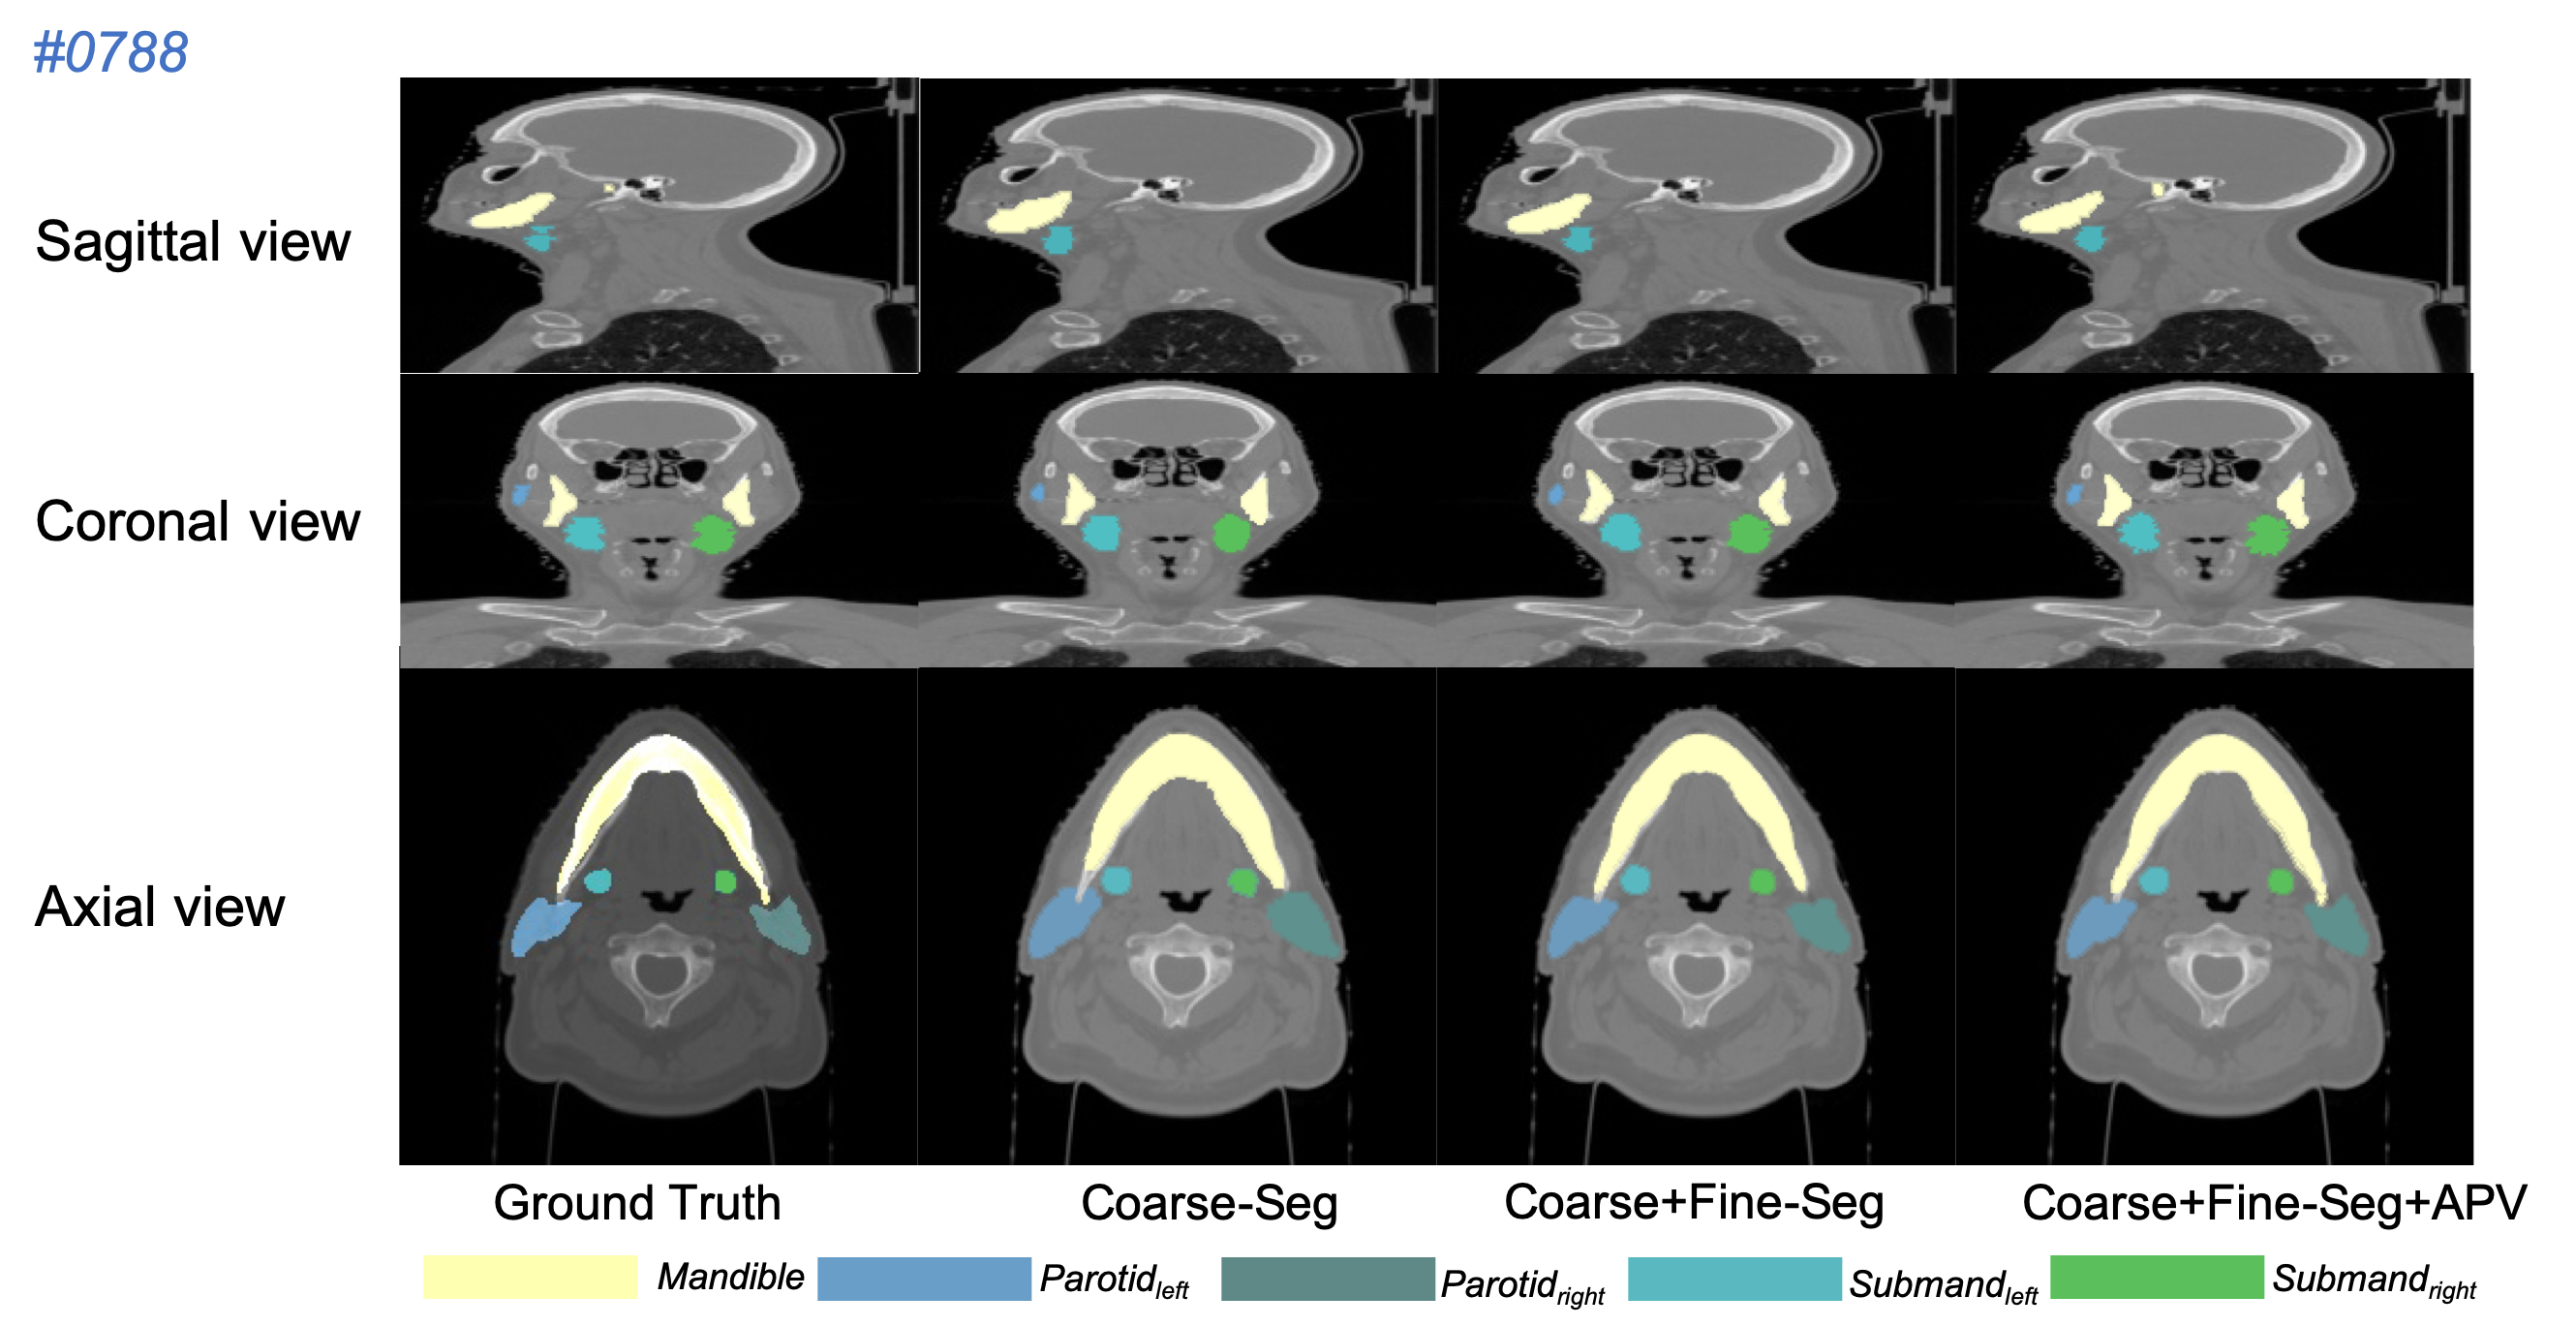

Refer to caption

Figure 5: Segmentation results of our proposed method on the PDDCA dataset.

The Quantitative comparison in Tab. 1 demonstrates that the proposed network outperforms several state-of-the-art architectures based on the average DSC (%) accuracy and is capable of segmenting organs from multi-classes robustly. Our coarse-to-Fine framework both without (Our-F) and with APV (Our-A) show competitive performance in direct comparison with the active appearance model method [19] and current learning-based approaches [13, 40]. Although [40] shares similar coarse-to-fine architecture but processes only on 2D slices in fine-scale segmentation, our based-model (Our-F) directly exploits 3D volumes and learns structural information so as to achieve a higher accuracy. Enhanced by APV module, the refined segmentation (Our-A) gets highest DSC accuracy among all reported methods. Test results on patient samples randomly selected from the PDDCA validation dataset (Fig. 5) visually illustrate that the proposed method gives three-level segmentation: (1) the coarse-scale segmentation (Fig. 5 Coarse-seg) predict a rough location and shape of the OARs; (2) the fine-scale segmentation (Fig. 5 Coarse+Fine-seg) estimates a detail boundary of each OARs but still with some flaws; (3) the APV-refined segmentation (Fig. 5 Coarse+Fine+APV-seg) generates 3D mask which is able to overlap the OARs perfectly.